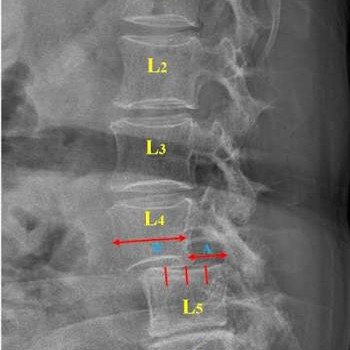

Low Back Pain and Physiotherapy Treatment at Sunshine Super Speciality Physiotherapy Clinic,